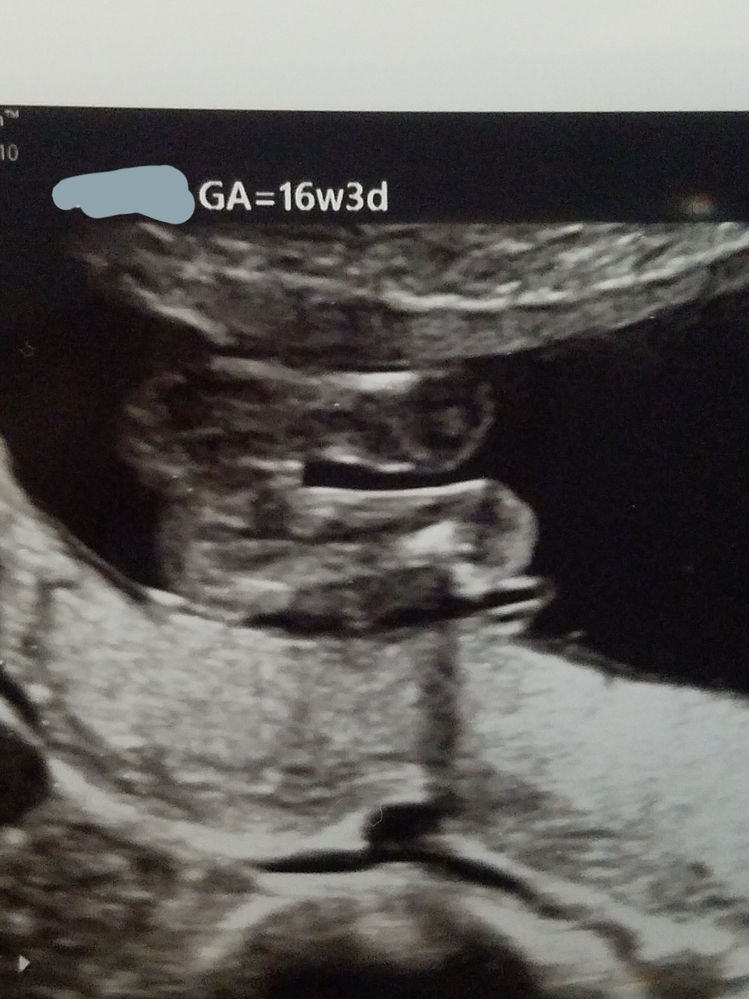

胎児の性別 16週の妊婦です この子の性別は女の子でしょうか 割れ目がある気がします

妊娠5ヶ月 性別はどちらに見えますか 妊娠5か月目 16w3d Yahoo 知恵袋